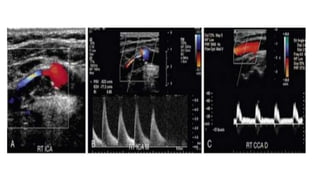

PSV- 195 CM/SEC PSV-96CM/SEC

PSV-305 CM/SEC PSV-85 CM/SEC

PSV- 195 CM/SECPSV-96CM/SEC

• #26 reveals echogenic plaque and a stenosis at the origin of the right ICA. Note color mosaic just distal to the narrowing of the vessel lumen indicative of increased velocity of flow in the post-stenotic jet